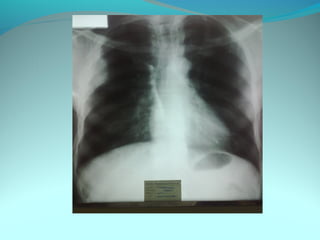

Opacité triangulaire a base cardiaque a sommet

axillaire dense et homogène

Par ailleurs on note

Une opacité plus dense que celle arrondie de 3cm de

diam hilaire gauche ;une surélévation de la coupole

diaphragmatique gauche é poche a aire gastrique

DIAGNOSTIC :

ADP hilaire gauche avec trouble de ventilation

Surelevation de la coupole G et de la poche gastrique

avec de clarté le médiastin

DIAGNOSTIC:

Hernie diaphragmatique paralysie du diaphragme